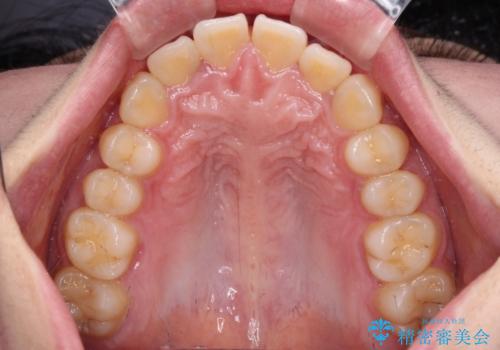

飛び出した上顎前歯 抜歯矯正でスッキリとした横顔に

- 下唇に跡がつくほどに飛び出した上顎前歯を気にして来院された患者様です。

来院された時から4本の抜歯が必要であることを理解されていらしており、通法通り上下左右の第一小臼歯4本を抜歯し、ワイヤー装置にて矯正治療を行うこととしました。

順調に治療が進み、2年弱で想定していたとおりの仕上がりにて治療を終えることができました。